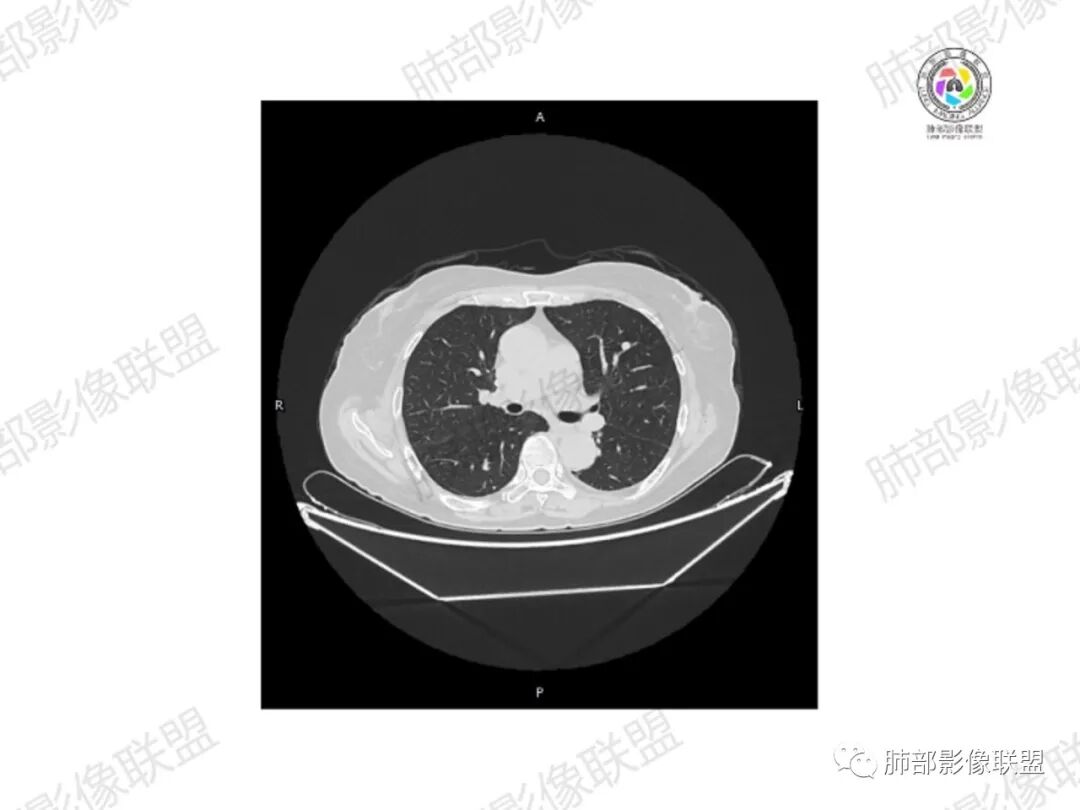

5.双肺多发类圆形结节影,边界清楚,随机分布,其间多见钙化密度影。

6.双肺门及纵隔未见肿大淋巴结。

3.双肺病灶符合转移瘤,伴有中央部分钙化者也以骨肉瘤转移较为多见。